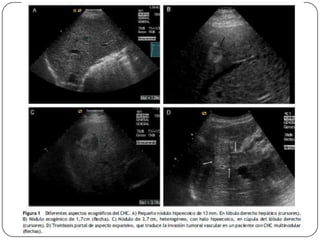

Auxiliares de diagnóstico

 USG

 Imágenes hipoecoicas, encapsuladas y con sombra

acústica, aunque en ocasiones aparecen como

alteraciones inespecíficas de la ecogenicidad, por

lo que resulta difícil diferenciarlas del daño

hepatocelular crónico.

 Sensibilidad (60-80%), Especificidad (45-96%)

 La sensibilidad en el CH alcanza 86%, pero en

lesiones menores de 2 cm es baja.

 Cada 6 meses en pacientes hepatópatas